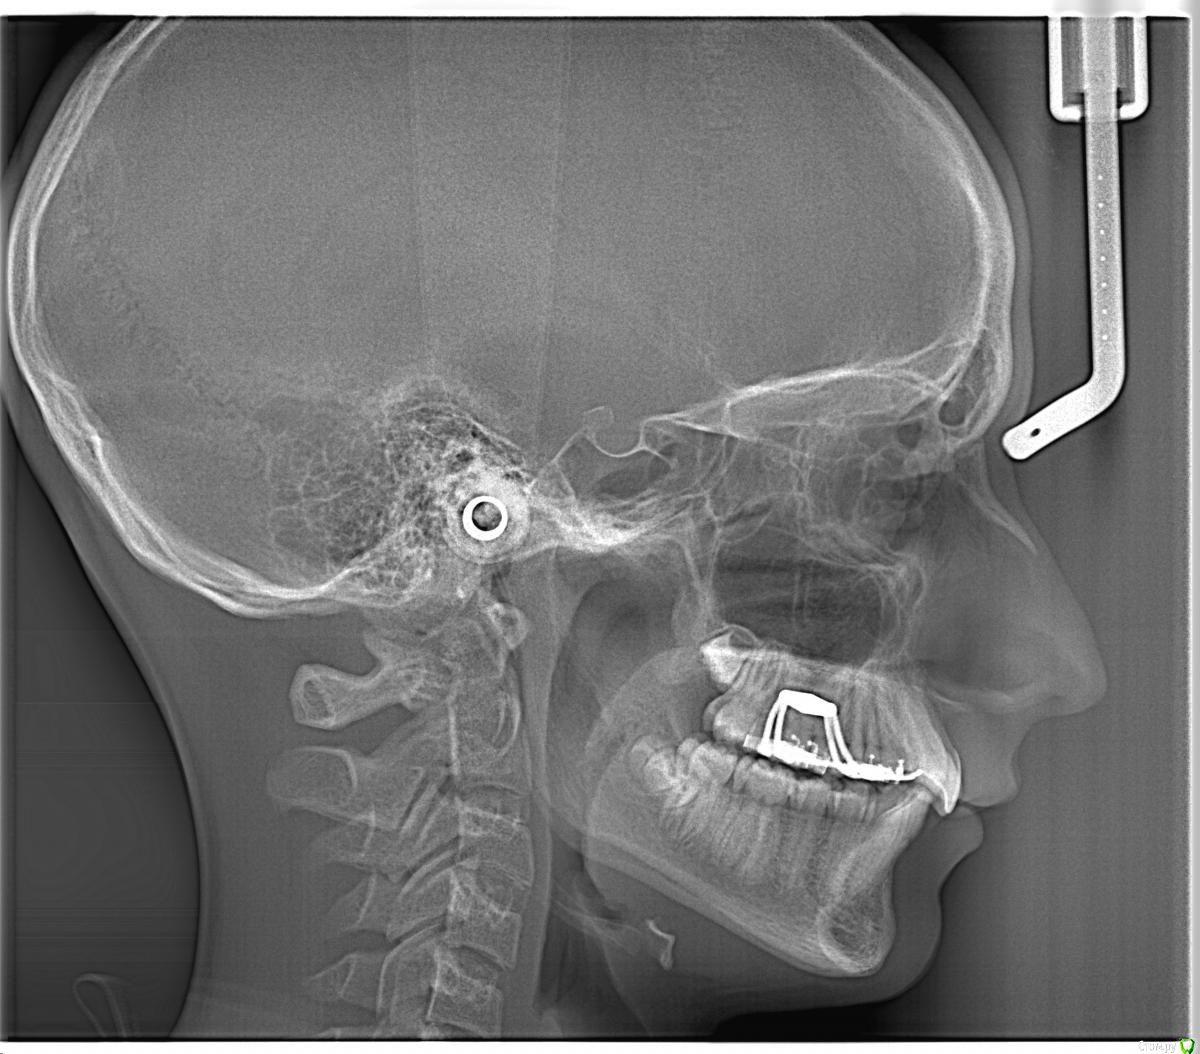

natkoorth1991 Опубликовано 28 августа, 2015 Поделиться Опубликовано 28 августа, 2015 мальчик, 13 лет, премоляры удалять не хотели, поставила хайракс на в / ч- получила перекрестную окклюзию. Извините за плохие фото( Что теперь делать? фото после: Ссылка на комментарий

Yana guapa Опубликовано 29 августа, 2015 Поделиться Опубликовано 29 августа, 2015 конечно, показаний для PRE здесь не было. но раз уж поставили, то поставили.Я бы теперь скручила винт в обратную сторону. будет нужный результат. Потом сняла бы аппарат и просто сделала бы перерыв. Премоляры сами немного вернуться к исходному положению Нет ТРГ. Но стакой инклинацией верхних центральных резцов могу предположить, что НЧ смещена кзади. Если это выяснится, и в ходе лечения НЧ будем перемещать вперед, то это тоже поспособствует лучшему смыканию. ждем снимков 2 1 Ссылка на комментарий

natkoorth1991 Опубликовано 29 августа, 2015 Автор Поделиться Опубликовано 29 августа, 2015 брекеты на вч не ставить пока? или зафиксировать и раскручивать обратно. По моделям там есть смещение нч где-то на половину бугра. На трг отправлю. Ссылка на комментарий

natkoorth1991 Опубликовано 2 сентября, 2015 Автор Поделиться Опубликовано 2 сентября, 2015 фото и трг Ссылка на комментарий